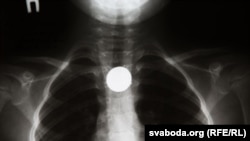

An X-ray, from Belarus's Scientific and Practical Center of Pediatric Surgery, showing a swallowed coin.

MINSK -- The reintroduction of coins in Belarus has led to a dangerous rise in consumption -- by children requiring medical attention to remove kopeks they have swallowed.